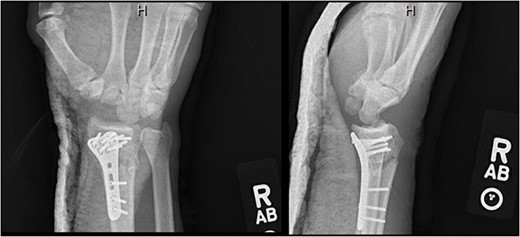

After medical optimization, the patient underwent PRC, open reduction internal fixation (ORIF) of the right distal radius fracture, and carpal tunnel release. A dorsal approach was used, with the third and fourth extensor compartments being released. At this point, extensive disruption of the dorsal wrist capsule and proximal carpal row was observed. The lunate was identified, noted to be devoid of soft tissue attachments, and was able to be excised. Completion of the PRC was achieved by excising the scaphoid and triquetrum from their minimal remaining soft tissue attachments entirely through the dorsal approach (Fig. 3). The lunate fossa of the radius, proximal capitate, and radioscaphocapitate ligament (prerequisite for successful acute PRC) was noted to be intact [2].

AP and lateral views immediately postop demonstrating right distal radius fixation and PRC.